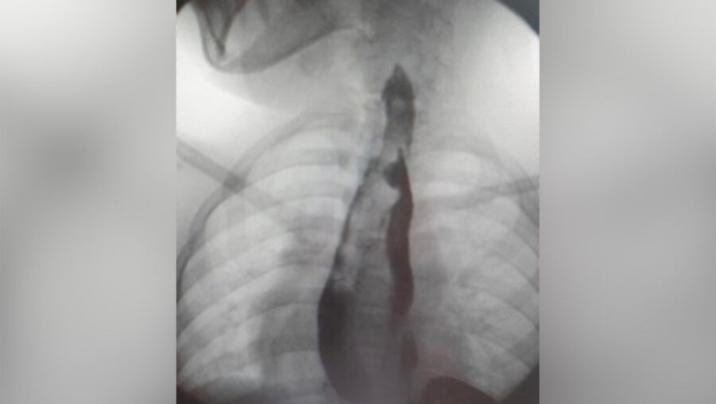

14 yaşlı məktəbli qız qarın nahiyəsində vaxtaşırı ağrılardan şikayətləndiyi üçün ailə yaşadıqları yer üzrə klinikaya müraciət edib. Müayinə zamanı nadir bir patoloji - yemək borusu və mədənin qoşa olması aşkarlanıb.

Hər iki cüt orqan, demək olar ki, bütün uzunluğu boyunca tam formalaşıb. Qız sonrakı müalicə üçün Moskvadakı Rusiya Uşaq Klinik Xəstəxanasına göndərilib.

“Klinik praktikada ən çox rast gəlinən növ həzm traktının kiçik bir hissəsinin kistik təkrarlanmasıdır. Ən çox da hallarda nazik bağırsağın. Həm özofagusun, həm də mədənin belə genişlənmiş ikiqat artması, hətta xarici təcrübədə də olduqca nadir bir vəziyyətdir. 40 illik təcrübəmizdə heç vaxt belə böyüklükdə patologiyaya rast gəlməmişik”, - Rusiya Uşaq Klinik Xəstəxanasının döş qəfəsinin rekonstruktiv və rekonstruktiv cərrahiyyəsi şöbəsinin həkimi Sergey Makarov bildirib.